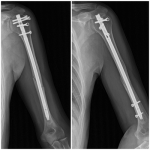

Fracturas diafisarias de húmero tratadas con un clavo MultiLoc®. Resultados a mediano plazo

Miguel Zublin, Matías Beatti, Diego Guichet, Tomás Pellecchia, Ignacio Arzac Ulla